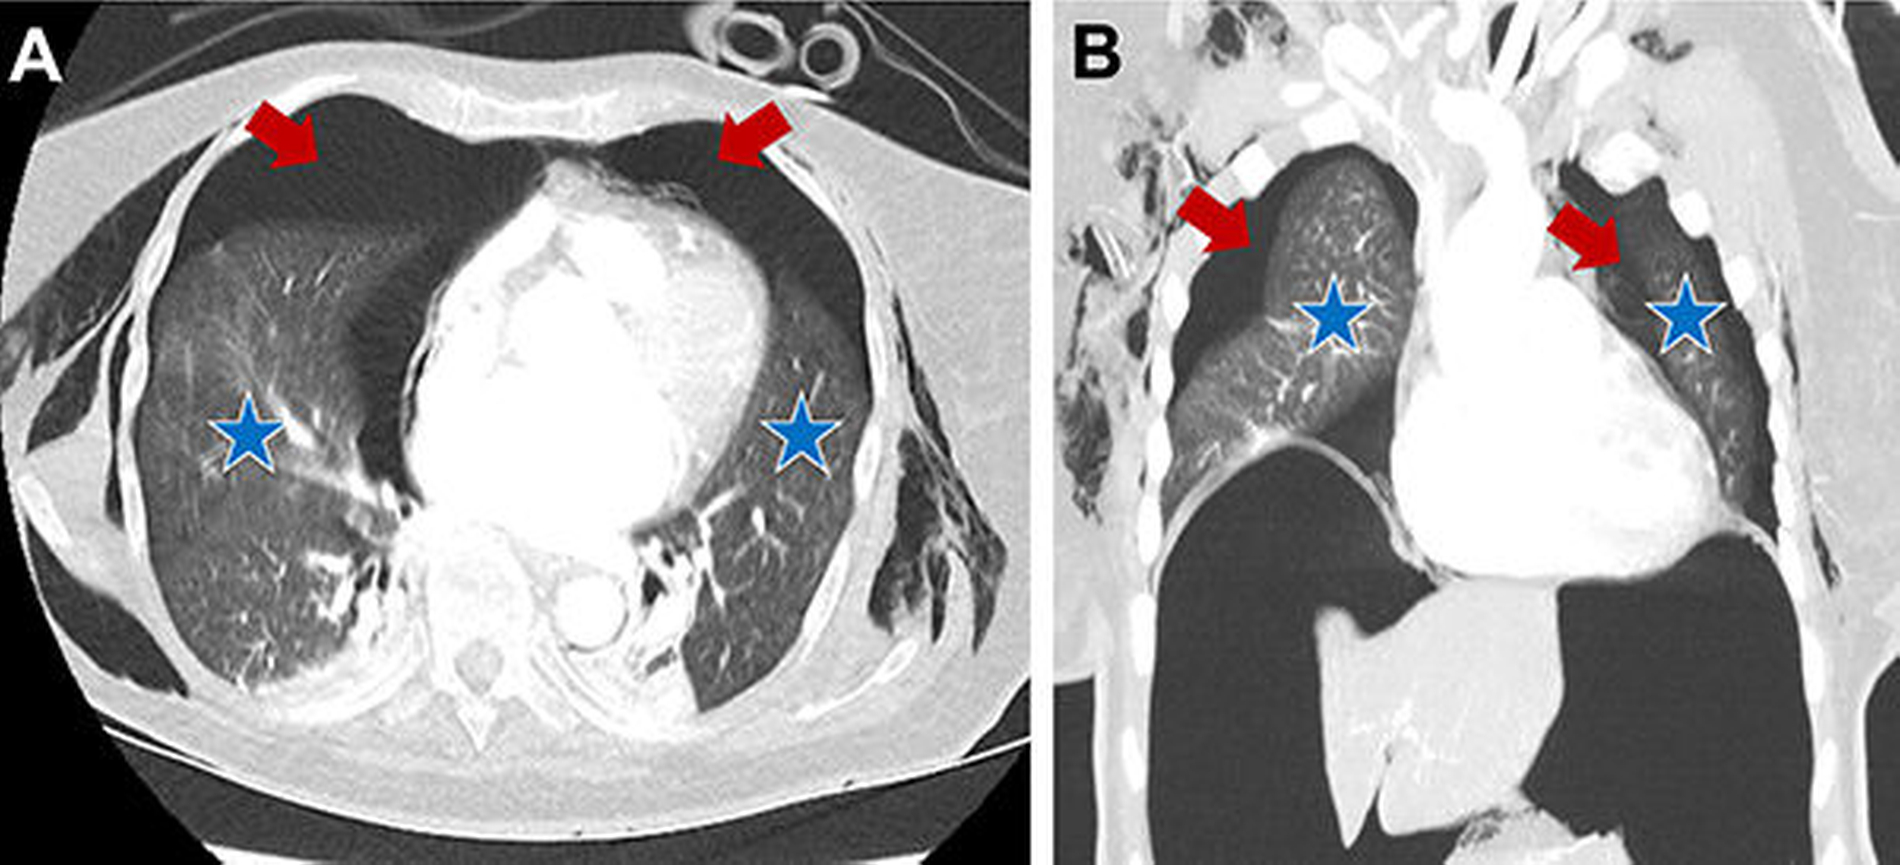

Im Rahmen der sofort eingeleiteten kardio-pulmonalen Reanimation erfolgte die unmittelbare Reintubation der Patientin, die einen schnellen ROSC (return of spontan circulation) zur Folge hatte. Im Zuge der durchgeführten Reanimationsmaßnahmen und der vorbestehenden Osteoporose kam es zu einer linksseitigen Rippenserienfraktur der Costae 3-7 (Abbildung 1), die einen beidseitigen Spannungspneumothorax und ein Pneumoperitoneum über eine Zwerchfellleckage nach sich führte.

Der Spannungspneumothorax wurde akut per Nadeldekompressionen und dann über Thoraxdrainagen beidseits entlastet. In der anschließend durchgeführten CT-Untersuchung von Thorax und Abdomen zeigte sich neben dem beidseitigen, entlasteten Mantelpneumothorax zusätzlich ein Pneumomediastinum mit Luftansammlungen im oberen, ventralen und dorsalen Mediastinum (Abbildung 2), zusätzlich dazu eine Ansammlung von freier Luft im Abdomen (Abbildung 3).